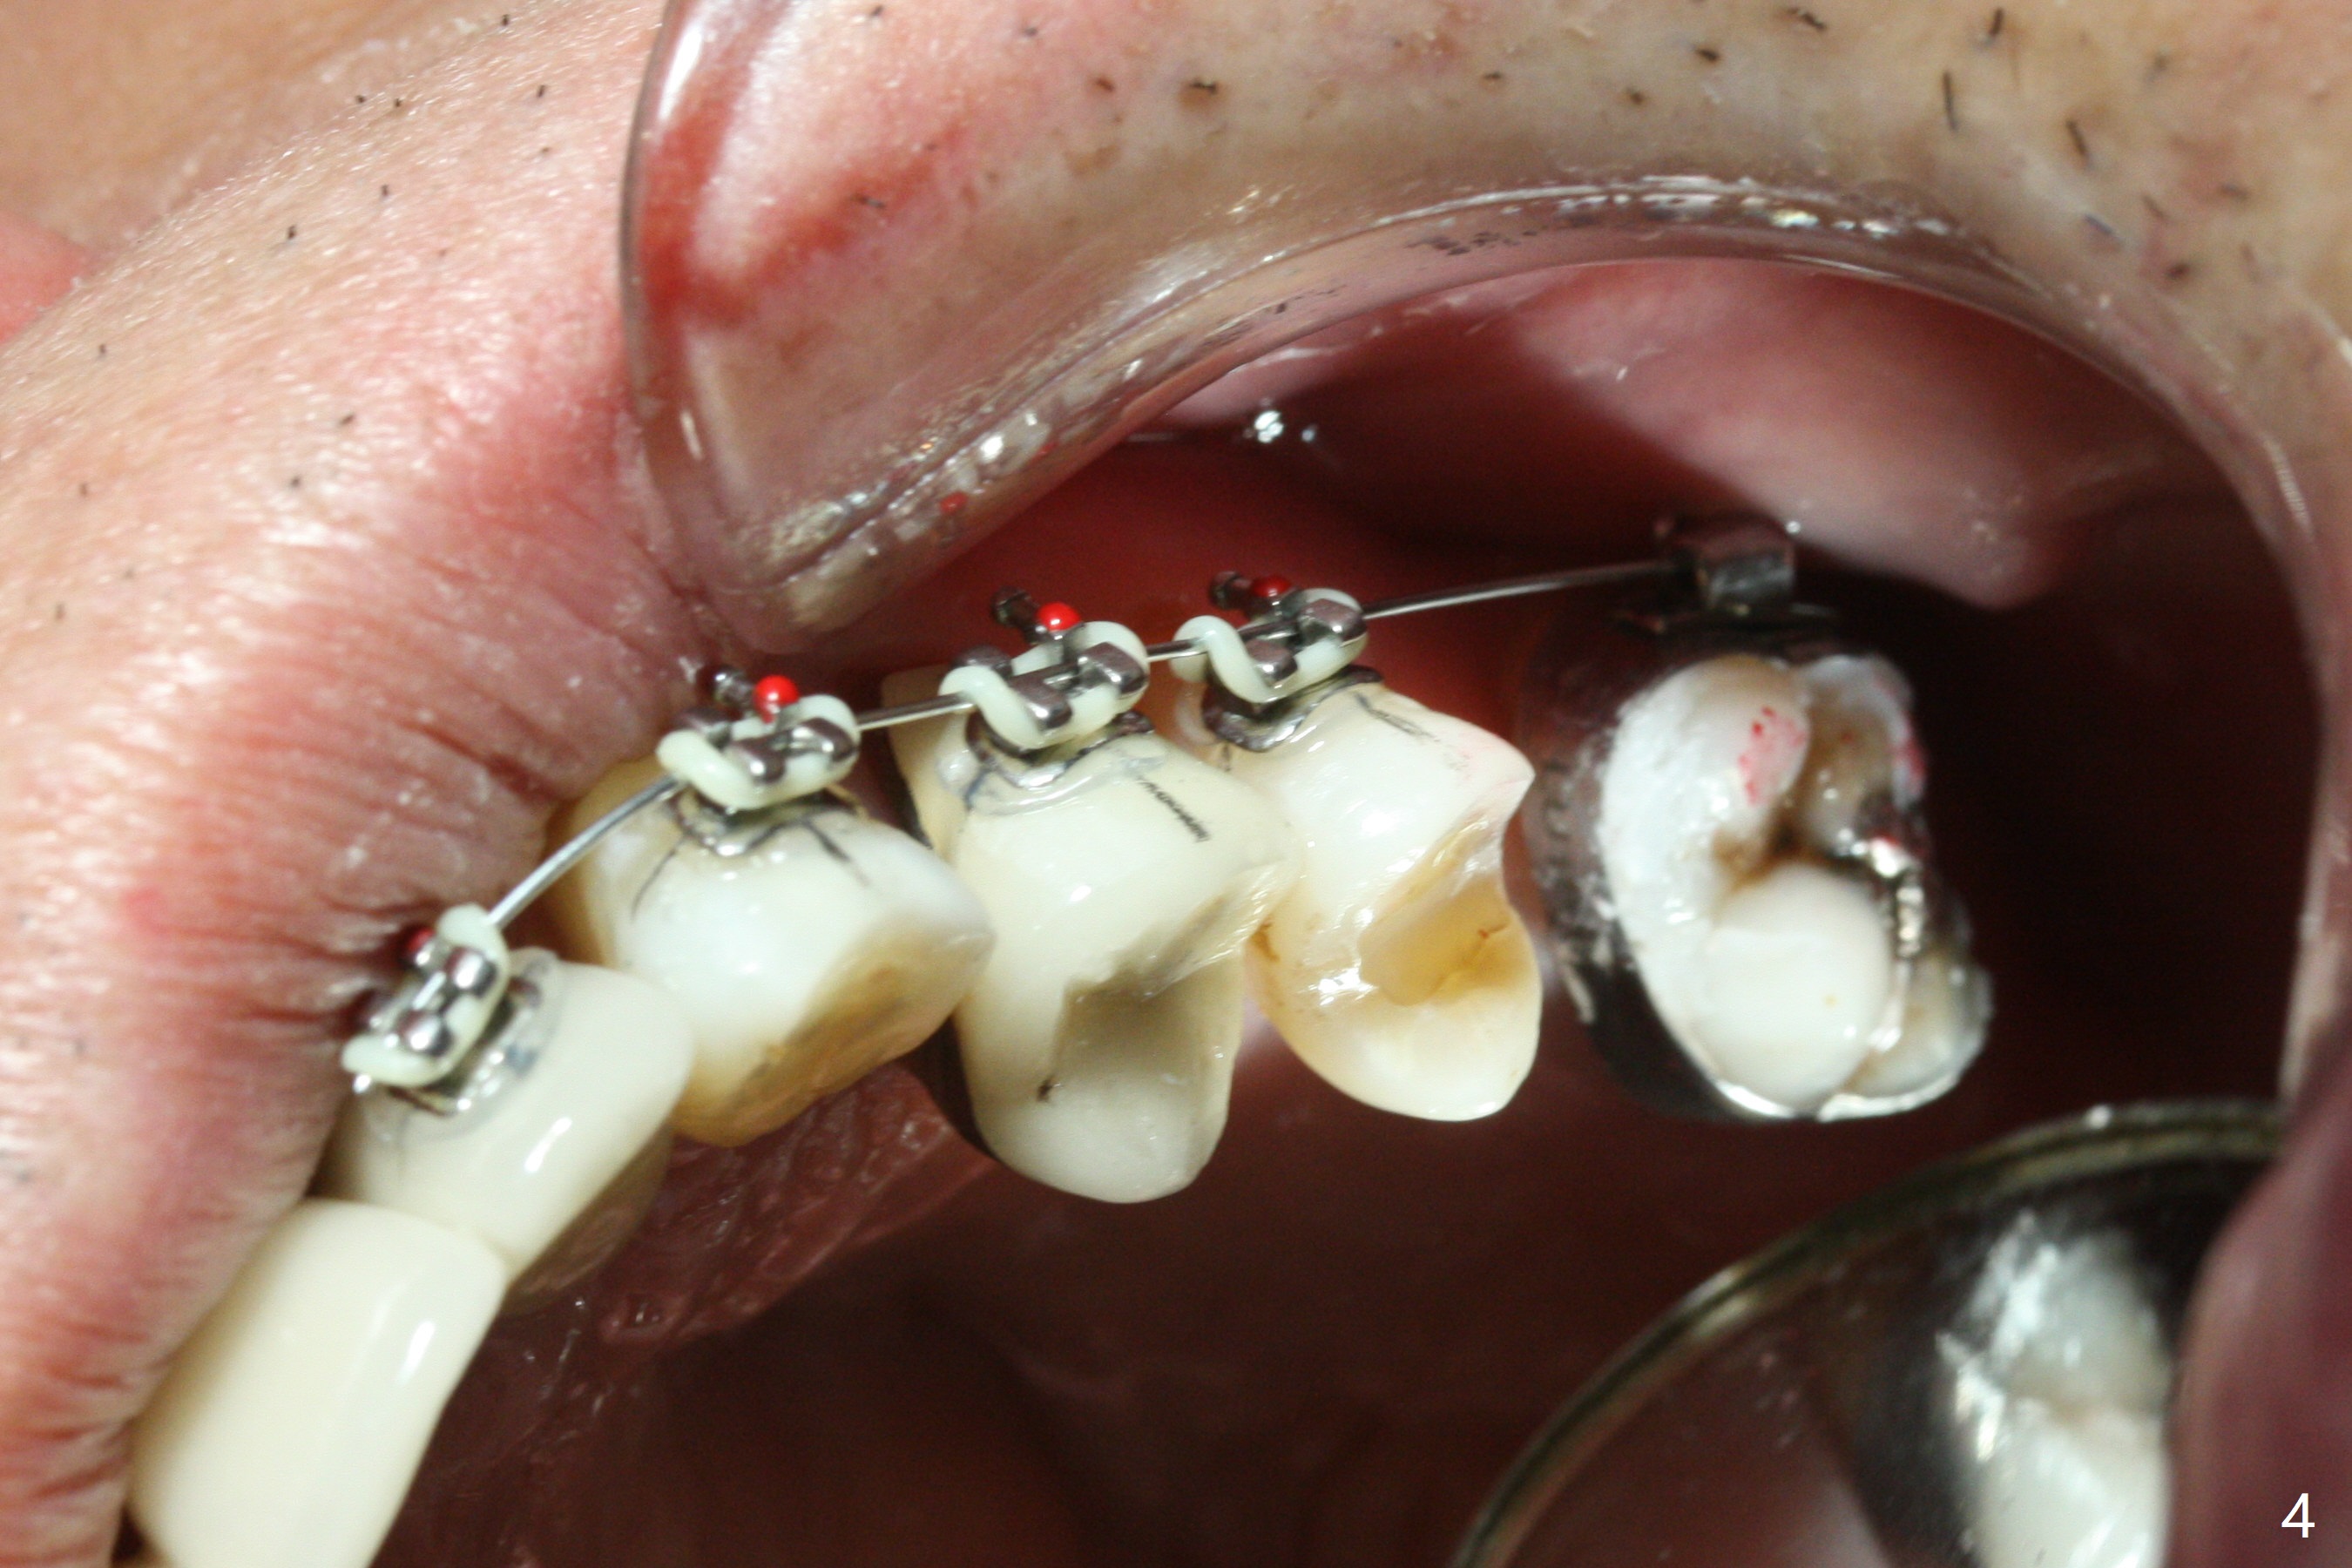

Ultradent Prime and Bond is used bracketing. The bonding system appears to be able to attach the brackets to porcelain crowns at #10 and 12 (Fig.3 (14 niti wire)). The 14 niti wire is not fully engaged (Fig.4). An open coil spring is used when the wire changes to 18 ss (Fig.5,6). Composite is placed to have clearance for UL7 to be distalized (Fig.5 *). To have the best anchor involving the implant at UL2, ligature wire is used between UL2-5 (Fig.6). In fact the anterior teeth are not good anchor. The bracket detaches from UL2 (implant) and UL5 keeps rotated, while UL7 is not distalized when open coil spring is placed between UL5-7. Nearly 6 months post banding, a 1.6x8 mm anchor pin is placed (Fig.7,8). Next visit the pin is loose and replaced with a ball type 1-piece implant (2x10(2) mm). Although the latter remains apparently stable, UL7 appears to remain in place. It seems necessary to place a restorative implant at UL6 as a future anchor (Fig.9: 3.5x11.5 mm).